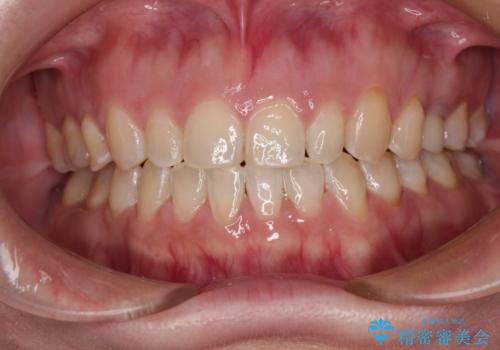

- 前歯の叢生と八重歯を気にして来院された患者様です。

叢生が強く、奥歯の咬合も左右差が大きかったため、上下左右4本を抜歯して、ワイヤー矯正を行うこととしました。

奥歯の咬み合わせを改善したいため、治療期間が長くなりましたが、患者様には辛抱強くお付き合いいただきました。

上下の正中を合わせることもでき、患者様には大変満足していただきました。